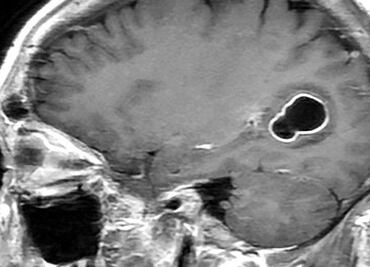

La compañía emergente, cofundada por Musk en 2016, pretende desarrollar un canal de comunicación directa entre el cerebro y las computadoras, con el fin de, en una fase inicial, devolver la autonomía a personas con necesidades médicas

El chip fue entrenado con un método de inteligencia artificial llamado red neuronal, que decodifica palabras según la actividad cerebral que se produce cuando intenta articularlas

Con lo anterior, Noland Arbaugh se convierte en el primer ser humano en usar el implante cerebral para controlar el cursor o el teclado de un computadora utilizando únicamente sus pensamientos